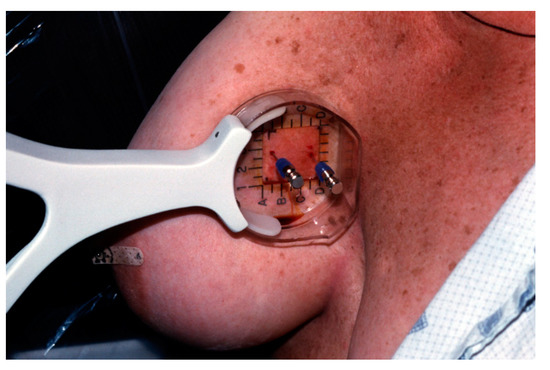

Figure 15. Intraoperative localization of a SLN using a Gamma Probe (Neoprobe 1500, Neoprobe Corp., Dublin, OH, USA). The mark on the skin of the axilla was made following lymphoscintigraphy.

9. Intraoperative Sentinel Lymph Node Biopsy

The suitable timing for radiopharmaceutical injection ranges from 2 to 24 h prior to surgery [40]. Immediately prior to surgery, 2.5 to 7.5 mL of isosulfan blue dye is injected into the tumor bed in the operating room. A hand–held gamma detection probe is used to assist in SLN detection (Figure 15). Radioisotope injection allows the surgeon to localize the sentinel node prior to making an incision and blue dye enables the surgeon to visually identify the SLN or an associated lymphatic channel. Different criteria for the identification of SLN exist in the medical literature [13], including; lymph nodes with an acoustic signal, a discrete area of radiopharmaceutical uptake separate from the injection site with counts of at least 25 in 10 s, lymph nodes that have sentinel to non-sentinel lymph node count ratios of greater than 10; and greater than or equal to 25 counts over 10 s ex vivo in the resected specimen. The inability to find a “hot spot” or a blue lymph node is considered a technical failure.